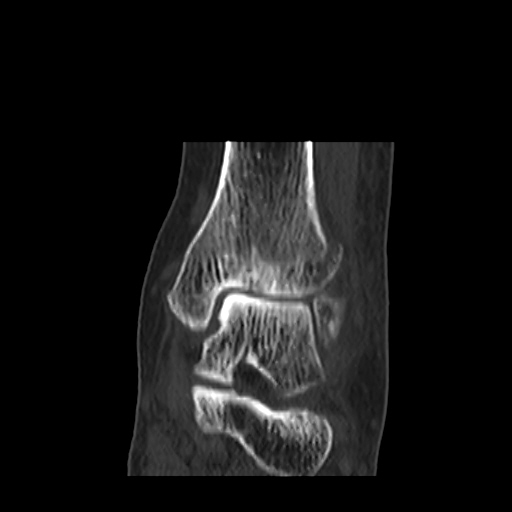

CT : avulsion fracture of distal tibia at distal tibiofibulat ligament insertion.

short leg splint with crutch gait